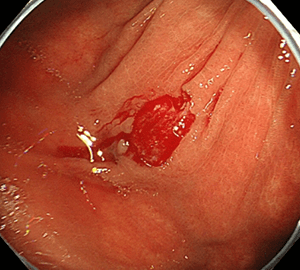

5:切除します。切除検体は吸引回収し、病理検査を行います5:切除します。切除検体は吸引回収し、病理検査を行います。

6:切除後に洗浄・観察して、病変の遺残がないことを確認します。6:切除後に洗浄・観察して、病変の遺残がないことを確認します。